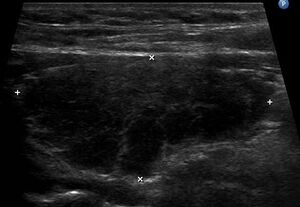

The thyroid of someone with Hashimoto's thyroiditis as seen with a microscope at low magnification | |